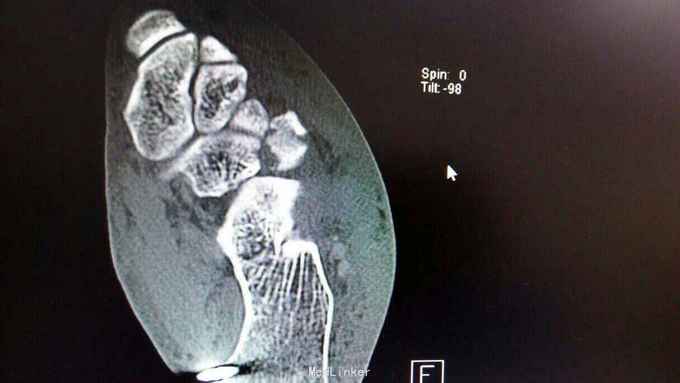

距骨骨折并脱位

骨折 距骨骨折

重物砸伤左足疼痛畸形14小时。

左踝至中足肿胀,左足内翻畸形,皮肤可见少许细小水泡,压痛,足背动脉搏动可,足趾活动可,感麻木。

距骨骨折并脱位 入院行闭合手法复位失败,予以跟骨牵引5天,石膏外固定3天,皮肤水泡、肿胀消退后行,距骨骨折脱位切开复位内固定+距舟关节融合。术后支具外固定,勿负重3个月。